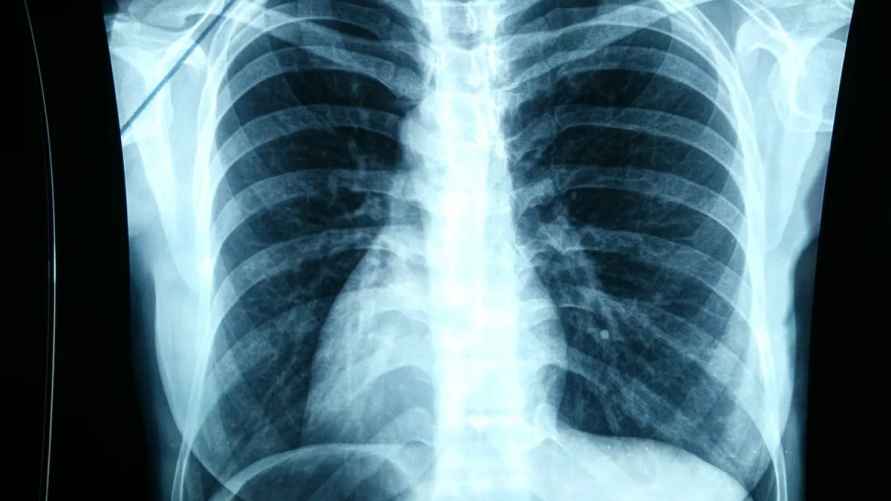

- электрокардиограмму;

- рентигенфлюорографическое обследование.